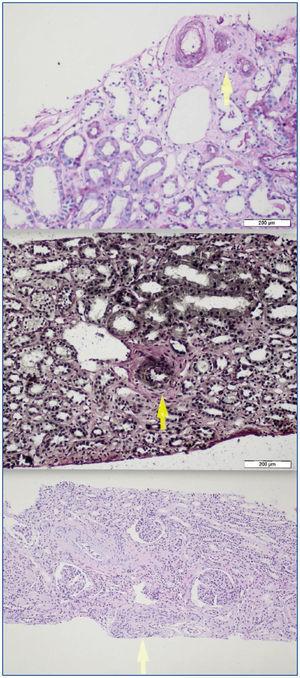

A 26-year-old man presented with a few weeks history of nausea, malaise, blurred vision, a brief episode of visual loss and hypertension. While working, he experienced loss of sight but regained it after a couple of minutes. He had no history of chronical disease. Family history of patient was not contributory-without a family history of vascular disease or hypertension. He was not taking any medications and denied any heavy alcohol, cocaine or intravenous drugs use, but had a 10-pack-year tobacco history. On review of systems, he reported 6-7 kilograms of unintentional weight loss in the past one year. Blood pressure was 150/70mm/Hg, a temperature of 36.8oC, heart rate of 64/min, and respiratory rate of 16/min. Cardiovascular and respiratory system examination was not remarkable. Indirect ophthalmoscopy was performed; retinal detachment (exudative) in both eyes, raised papilla limits, retinal vessel tortuosity, choroidal hypopigmented lesions under retina and superficial haemorrhages were detected. Exudative retinal findings defined as Vogt-Koyanagi-Harada syndrome. Laboratory and ultrasonographic findings were shown at Table 1. Peripheral blood smear revealed; enough platelets with normal morphology, schistocytes were rare, reticulocytes <2%, normochromic normocytic red blood cells. Primary hematological disease was not considered. He was started to be investigated for primary hyperaldosteronism, Cushing's disease and pheochromocytoma. During the follow up in nephrology service, the patient had presyncope, convulsion, hypertensive emergency and altered mental function. His blood pressure was 220/110mm/Hg. Blood pressure was controlled via sodium nitroprusside infusion for 48 hours and amlodipine 10mg, nebivolol 5mg, doxazosin mesylate 8mg at following days in intensive care unit. After the neurology consultation was performed the patient was evaluated with magnetic resonance imaging (MRI). Bulbus, pons and left mesencephalon, basal ganglia, peri-supraventricular white matter areas of increased T2 signal is considered to be consistent with vasogenic edema. Subretinal haemorrhages were detected at posterior parts of both orbit. It was reported as posterior reversible encephalopathy syndrome (Figure 1). After 5 days of intensive care follow up the patient had normal blood pressure. After excluding frequently seen secondary hypertension causes, renal and mesenteric angiography was performed at the same time suspecting renovascular hypertension. Angiography revealed multiple microaneurysms involving the parenchymal branches of the celiac artery, bilateral renal artery and superior mesenteric artery (Figure 2 and Figure 3). After the angiography, eventually, ultrasound-guided renal biopsy was performed. Light microscopy revealed 9 glomeruli with no specific patterns except a slight increase in mesangial matrix. Normal interstisium, tubular focal atrophy and intimal-medial thickening of blood vessels was apparent. Due to increased cellularity obstruction and perivascular fibrosis were found in blood vessels. Histochemically, periodic acid-Schiff, M. Silver, Masson’s Trichrome staining was used. Congo red staining was negative. With direct immunofluorescence method, there was no specific deposition of IgA, IgG, IgM, C3, C4, C1q, fibrinogen, kappa and lambda. Histological diagnosis was reported as signs of vascular myointimal hyperplasia (Figure 4). With all these findings (clinical characteristics such as severe hypertension and renal insuficiency, constitutional symptoms such as malaise and weight loss, inflammatory parameters like elevated erythrocyte sedimentation rate-ESR and C-reactive protein-CRP, angiographic findings) the patient was diagnosed as PAN. Oral prednisolone therapy as 0.5mg/kg/day had been given. But as creatinine levels raised up and hypertension could not be well controlled with drug therapies, eventually hemodialysis was started (Figure 5).

Figure 4.